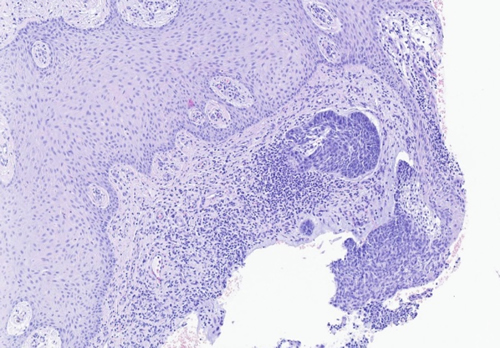

El resultado de anatomía patológica confirmó la sospecha de malignidad en el material remitido, informando de lesión compatible con carcinoma basocelular de patrón nodular (Figura 4), por lo que se deriva a servicio de dermatología para su evaluación completa y tratamiento quirúrgico con valoración de posterior tratamiento coadyuvante, si procede.

Figura 4. Imagen anatomopatológica de la lesión tumoral.

Por otra parte, la ecografía se ha demostrado como un método eficaz para la evaluación de la lesión, dado que es una técnica poco invasiva, aportando gran información a tiempo real acerca de tamaño y delimitación de la lesión(6). Al aportarnos una estimación de su dimensión nos permitirá mejorar los márgenes quirúrgicos y darnos una visión más global de la lesión(11). En la ecografía podemos observar los CBC como una lesión sólida de patrón hipoecoico, con bordes irregulares, pero bien definidos, que suele localizarse en la unión dermo-epidérmica; como característica propia del carcinoma basocelular, la lesión cuenta con puntos hiperecoicos intralesionales que no suelen tener refuerzo acústico posterior. El estudio doppler de las lesiones no suele mostrar una alta vascularización(6,8).